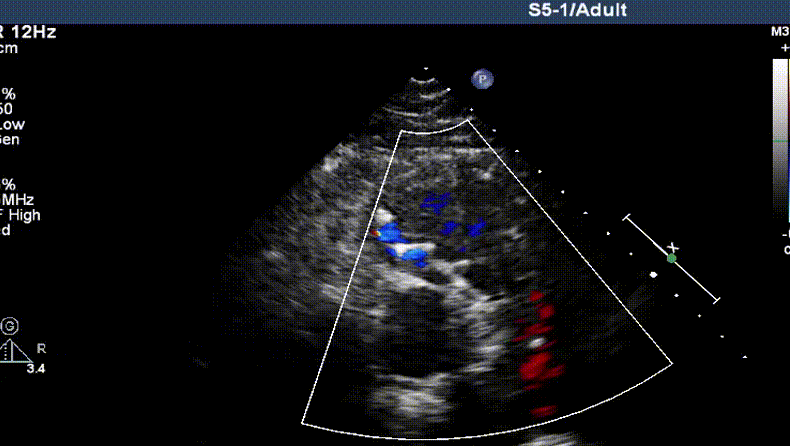

术后即可超声显示肺动脉瓣反流消失、瓣叶开闭正常

术后24小时超声显示瓣叶启闭功能正常